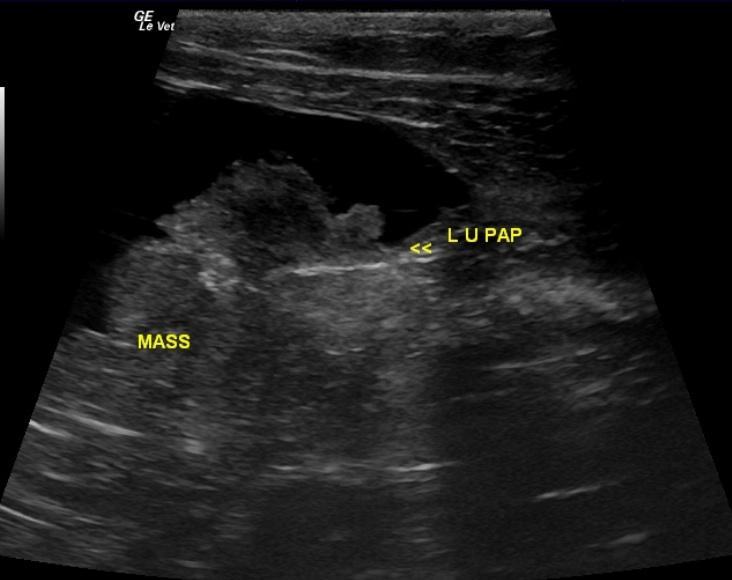

Bladder mass which is potentially resectable, but stent placement may be necessary. Pelvic dilation and pyelonephritis of the left kidney.

The urinary bladder contained a 3.3 x 1.34 cm mineralizing mass located at the dorsolateral aspect of the bladder and encroaching on the right ureteral papilla. Slight renal pelvic dilation was noted in the left kidney with moderate dystrophy and fibrosis. The right kidney was severely fibrosed and measured 2.7 cm.

BladdermassLeftureteralpapillaRightureteralpapilla